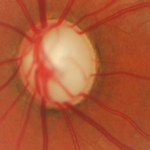

A missão da AbbVie é descobrir e fornecer medicamentos inovadores que solucionem os desafios mais sérios de saúde de hoje e enfrentem os desafios médicos de amanhã. Causamos um impacto notável na vida das pessoas em várias áreas terapêuticas: Imunologia, Oncologia, Neurociência, Oftalmologia, Virologia, Saúde da Mulher e Gastroenterologia, além dos serviços e produtos da Allergan Aesthetics.